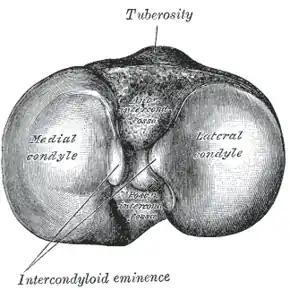

Upper surface of right tibia. (Tuberosity labeled at top.) | |

The tuberosity of the tibia, tibial tuberosity or tibial tubercle is an elevation on the proximal, anterior aspect of the tibia, just below where the anterior surfaces of the lateral and medial tibial condyles end.

The tuberosity of the tibia gives attachment to the patellar ligament, which attaches to the patella from where the suprapatellar ligament forms the distal tendon of the quadriceps femoris muscles. The quadriceps muscles consist of the rectus femoris, vastus lateralis, vastus medialis, and vastus intermedius. These quadriceps muscles are innervated by the femoral nerve.[1] The tibial tuberosity thus forms the terminal part of the large structure that acts as a lever to extend the knee-joint and prevents the knee from collapsing when the foot strikes the ground.[1] The two ligaments, the patella, and the tibial tuberosity are all superficial, easily palpable structures.[2]